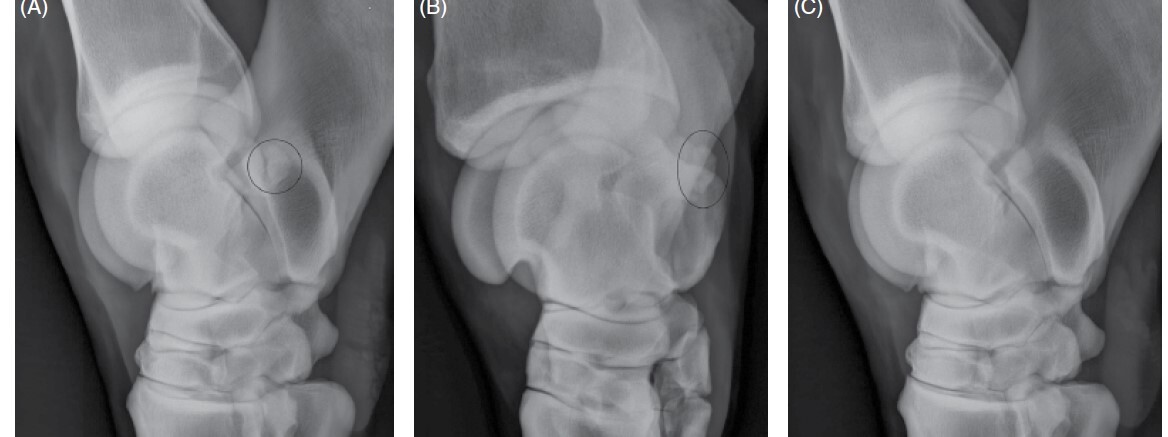

distal intermediate ridge of the tibia (DIRT) (Figure 99-24, A),

followed by the lateral trochlear ridge of the talus (see Figure 99-24, B),

Figure 99-24. (A) DMPLO radiographic view of the tarsus showing a distal intermediate ridge of the tibia OCD lesion. (B) DMPLO radiographic view of the tarsus showing a large lateral trochlear ridge OCD lesion.